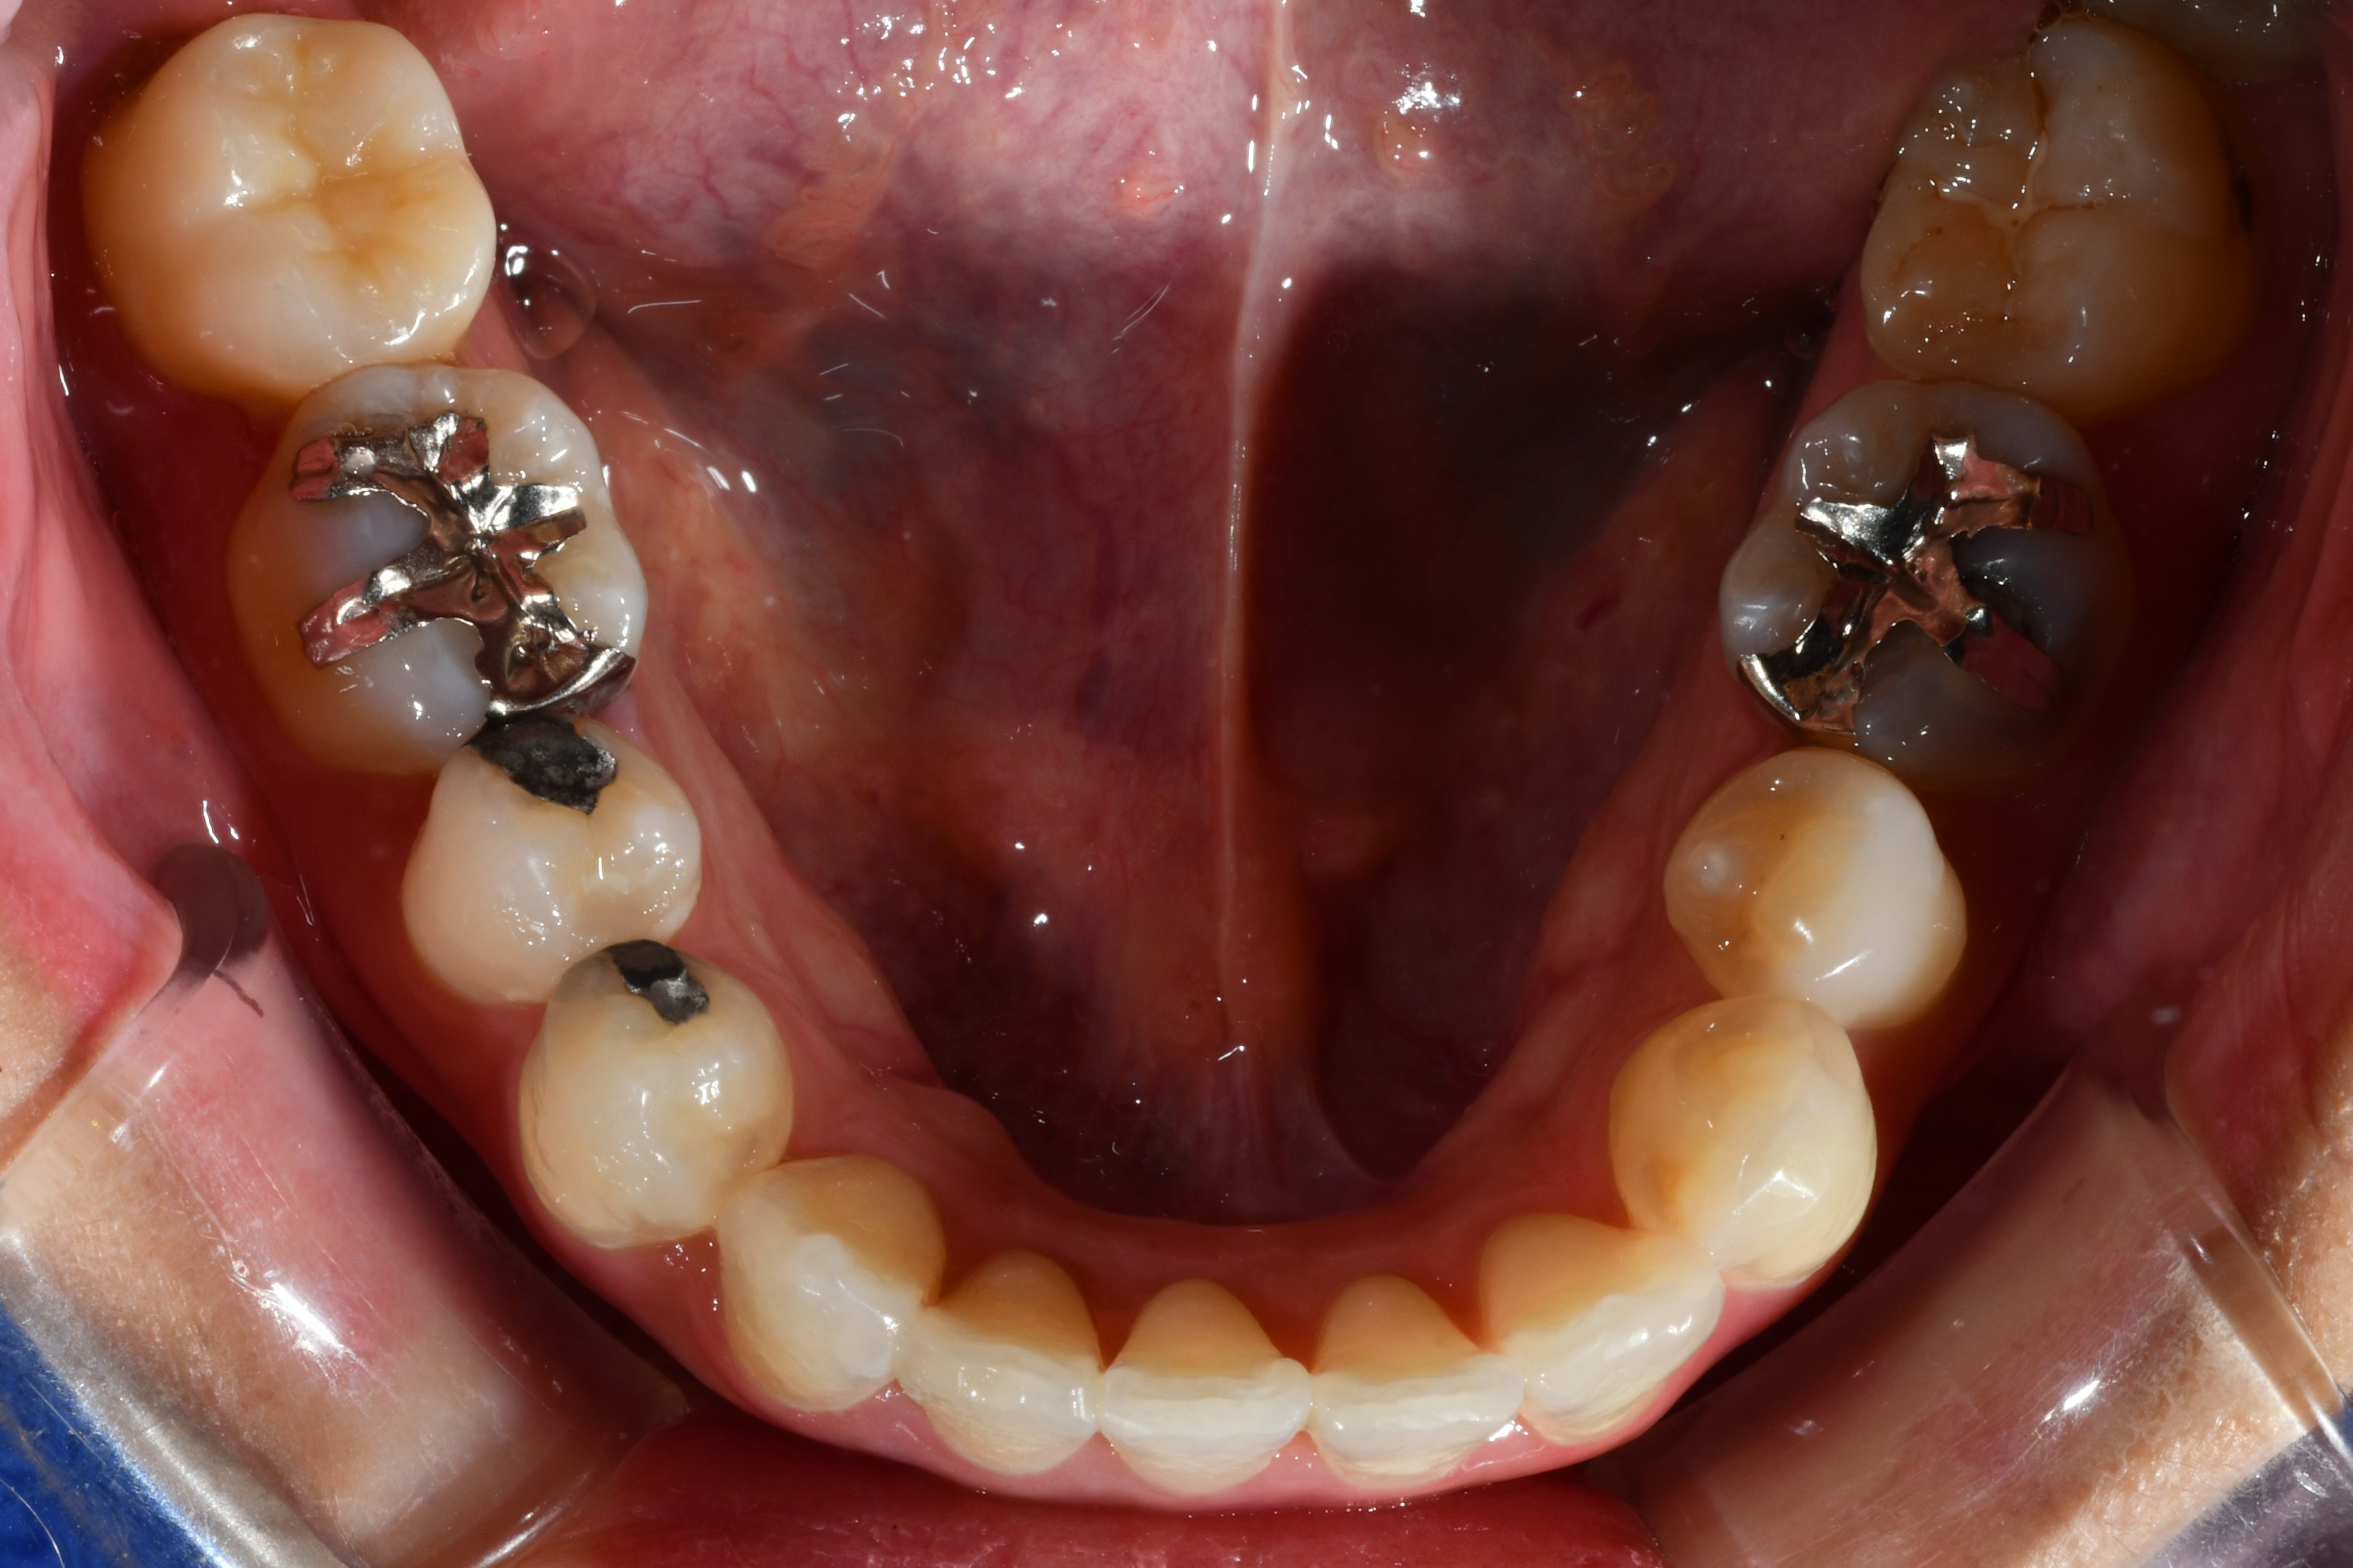

毎週自分で歯並びの写真を撮っていたので日々綺麗になっていく歯並びを見るのが嬉しく、家族からも綺麗になったねと言われました! マウスピース矯正と並行してホワイトニングも行っていたので、歯が格段に綺麗になるのを実感できたのが嬉しかったです。